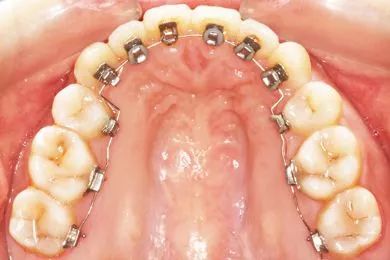

舌侧托槽:

是将托槽粘接在牙齿的舌侧面,可以达到很好的隐蔽效果。舌侧矫治技术对医生要求高,操作复杂,是正畸领域最高端的矫治技术。